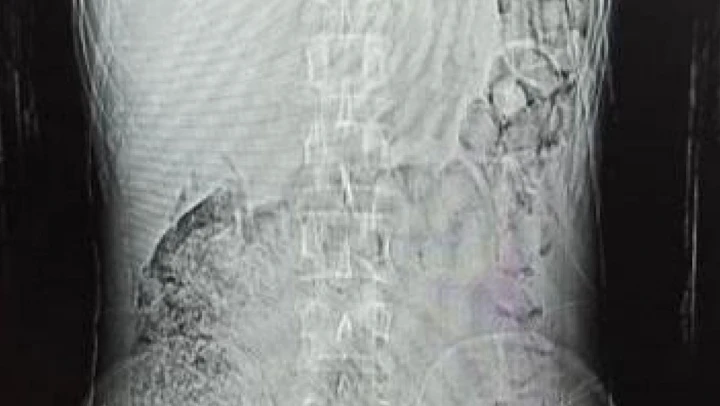

Edinilen bilgiye göre, Narkotik Suçlarla Mücadele ekiplerinin madde ticareti ve nakline yönelik yapılan çalışmalar sonucunda durumundan şüphelenilerek yakalanan ve uyuşturucu maddeleri yutarak nakletmeye çalışan İran uyruklu F.S. (30) yapılan iç beden muayeneleri sonucunda mide ve bağırsak kısmında 78 kapsül halinde 603,35 gr Afyon Sakızı ve 17 kapsül halinde 111,35 gr Metamfetamin maddeleri ele geçirildi.